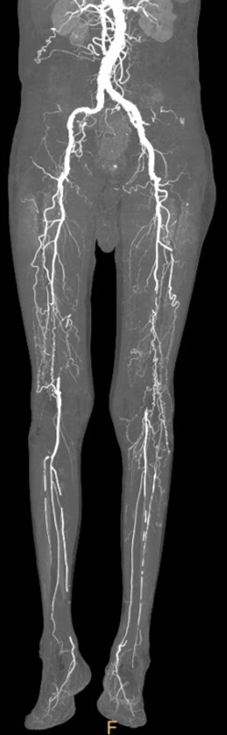

★ Case 5

Female,82 y

Severe claudication over 1 year in both extremities esp. in the left

DM over 10 years

CTA:SFA-PA long CTO

左右滑动查看